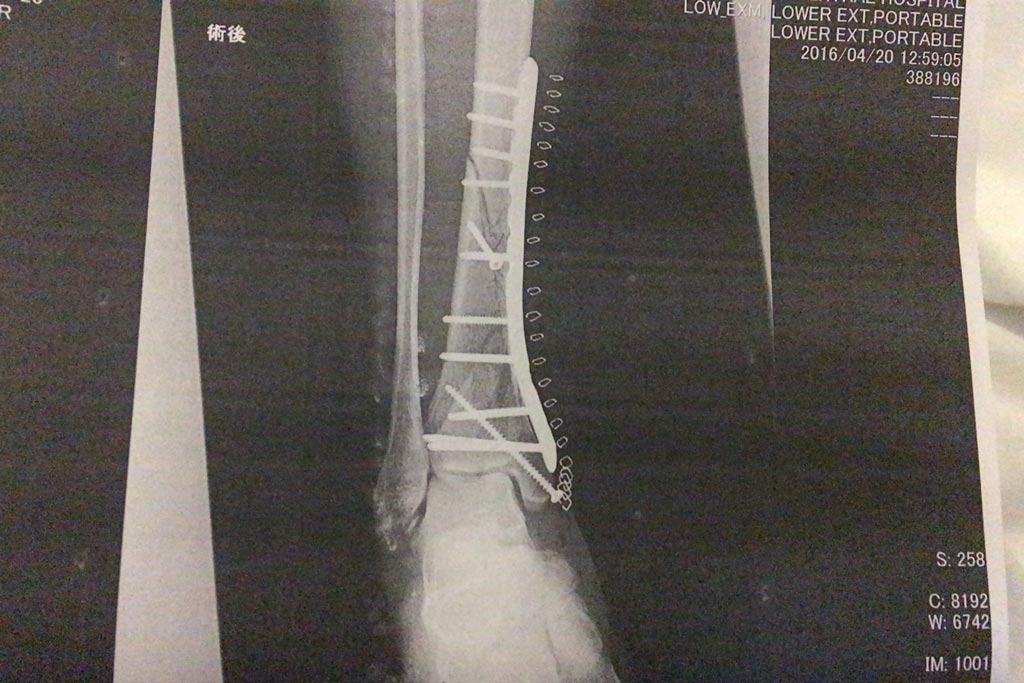

手術直後と退院する時のレントゲンを見比べても全然判らなかったけど、今回は素人目に見てもガッツリ骨がくっついてるのが見て取れて、だいぶテンションを上げ過ぎて『ちょっ!先生これちょっと写真撮って良いっすか写真!?』とか一人でキャッキャしてたら先生に笑われたf(^_^;)

あ、手術直後のレントゲンはこんなです。

粉々になった部分ほど密度が上がってるように見えるし、なんかエラいモリモリ盛り上がってるところとかあって、骨って樹木みたいですよね(笑)